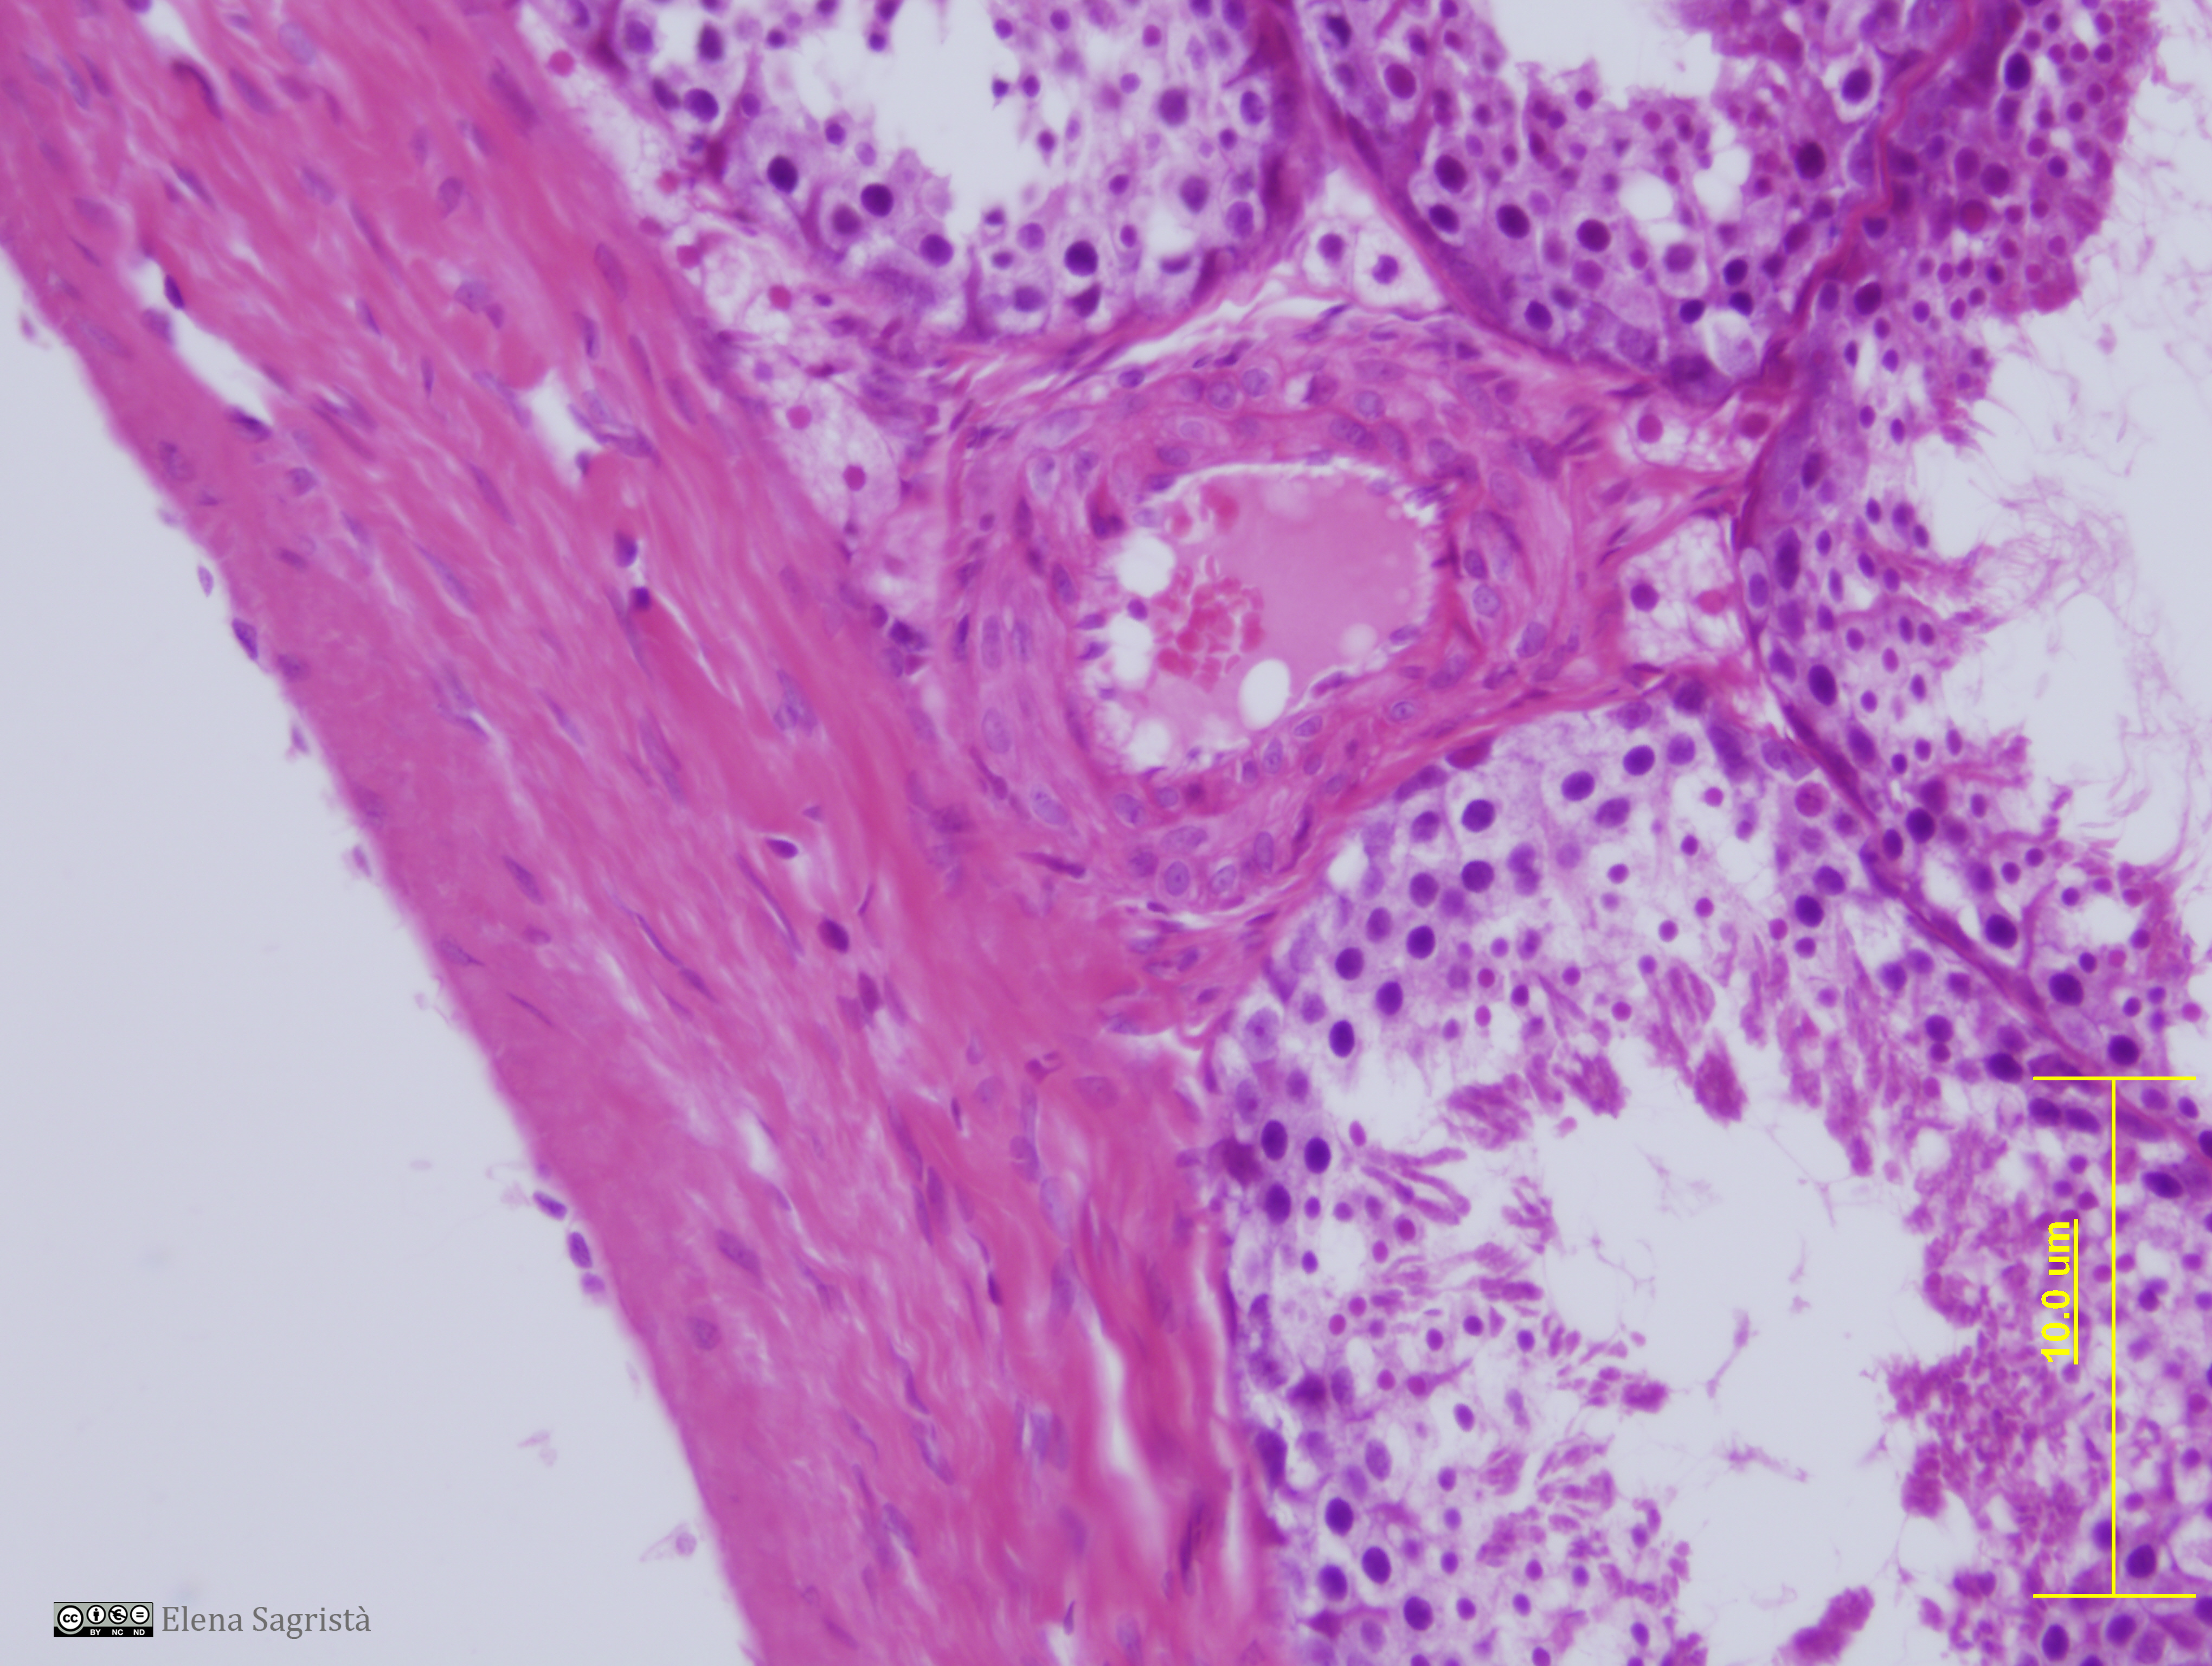

Histologia imatges: 02 Teixit conjuntiu

Imatges de preparacions histològiques de Teixit conjuntiu. Microscopia òptica.